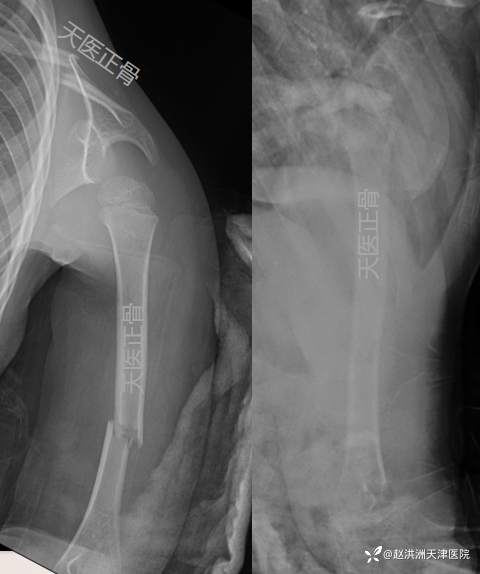

1周肱骨正位+穿胸位对位、对线同前

3周肱骨正位+穿胸位对位、对线可;断端可见骨痂,去除绷带